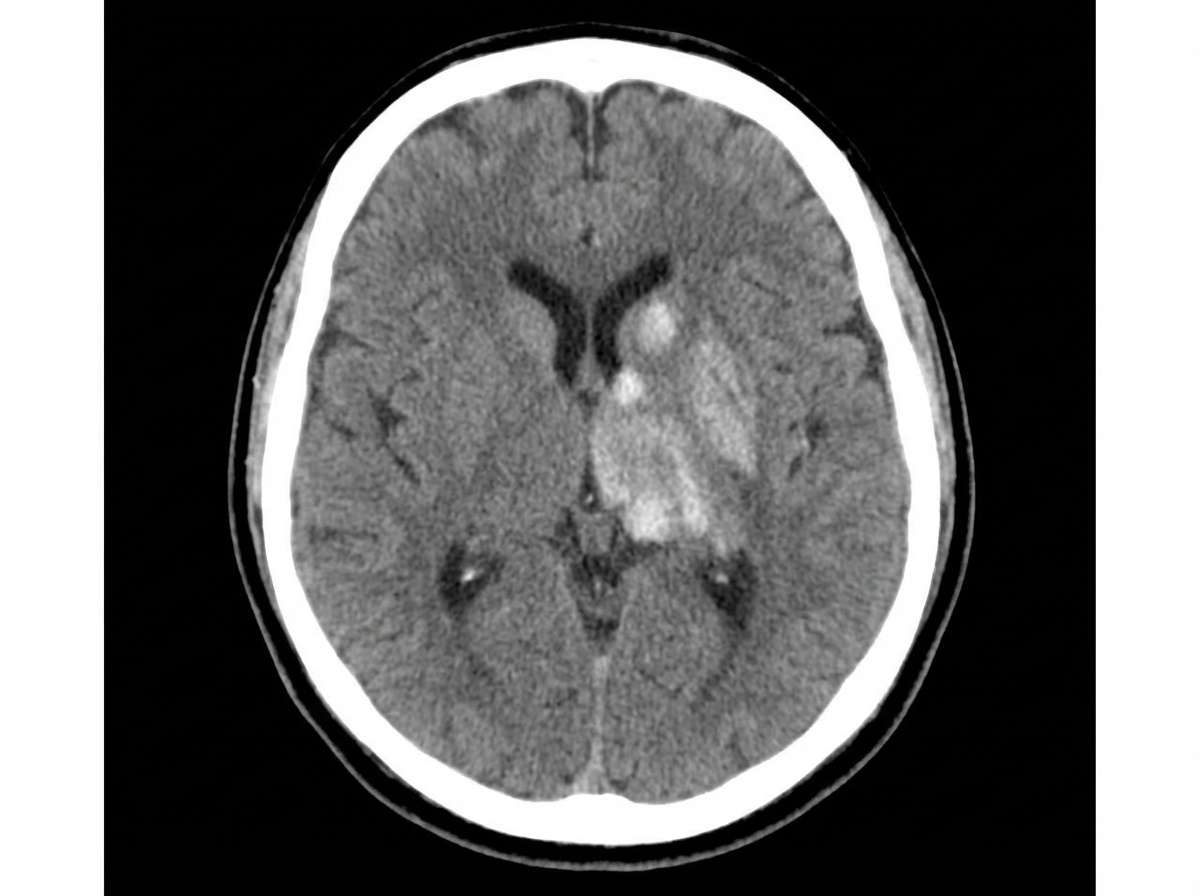

A patient presents with the CT finding shown in the image. Which one of the following signs is this finding most likely to produce?

Explanation: ***Hemiplegia*** - CT shows a lesion in the **internal capsule**, which contains the **corticospinal tract** responsible for motor control. - Damage to this area causes **pure motor hemiplegia** without sensory or cognitive deficits. *Uniocular blindness* - Requires damage to the **optic nerve** or **central retinal artery**, not the internal capsule. - Would present as **monocular vision loss** with an **afferent pupillary defect**. *Alexia without agraphia* - Results from lesions in the **left occipital lobe** and **splenium of corpus callosum**. - Patients can write but cannot read, requiring **disconnection** between visual and language areas. *Hemiballismus* - Caused by lesions in the **subthalamic nucleus** (body of Luys), not the internal capsule. - Presents as **violent, flinging movements** of the contralateral limbs due to **basal ganglia dysfunction**.